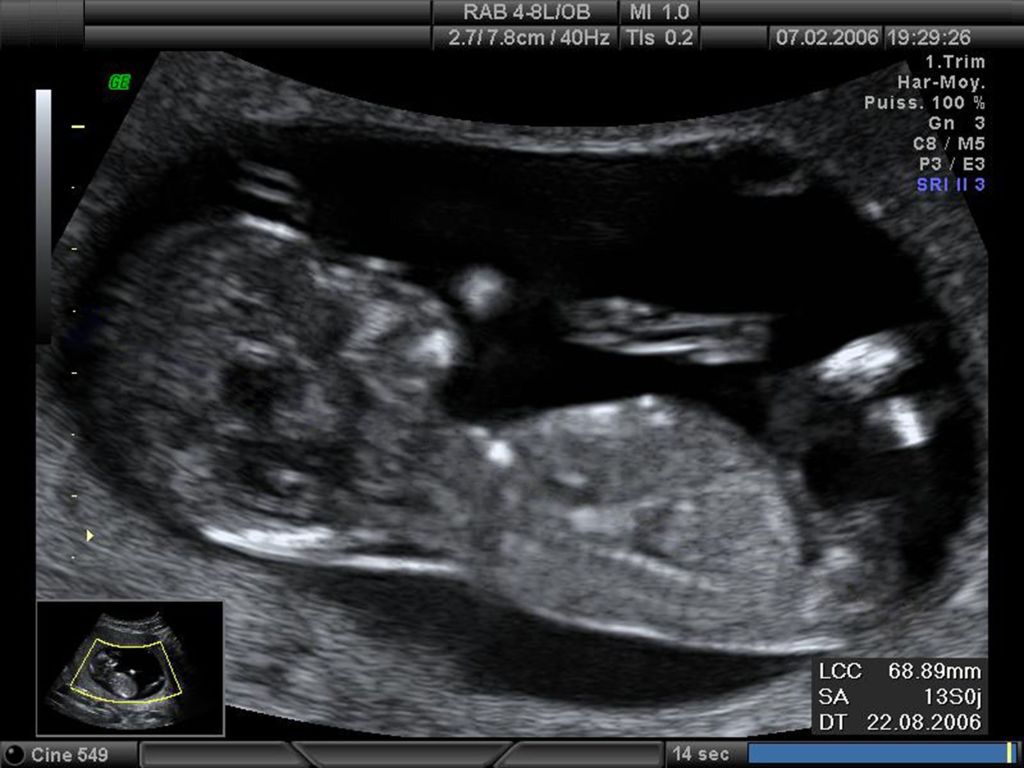

A második trimeszter ultrahangfelvételei már sokkal részletgazdagabbak. Ekkor láthatóvá válik a baba arca, gerince és belső szervei, az úgynevezett genetikai ultrahang pedig segít kiszűrni az esetleges rendellenességeket. A modern technológiának köszönhetően akár 3D vagy 4D képek is készülhetnek, amelyek szinte élethűen mutatják meg a magzat arcvonásait és mozdulatait.

A harmadik trimeszterben az ultrahangfotók már egy majdnem teljesen kifejlődött kisbabát ábrázolnak. Bár a hely szűkössége miatt a teljes test ritkán látható egyszerre, a részletek – például az arc mimikája vagy a kézmozdulatok – még inkább meghatóvá teszik ezeket a felvételeket. A 40. hét környékén készült képek már a születés előtti utolsó pillanatokat örökítik meg, így különleges emlékként szolgálnak a család számára.